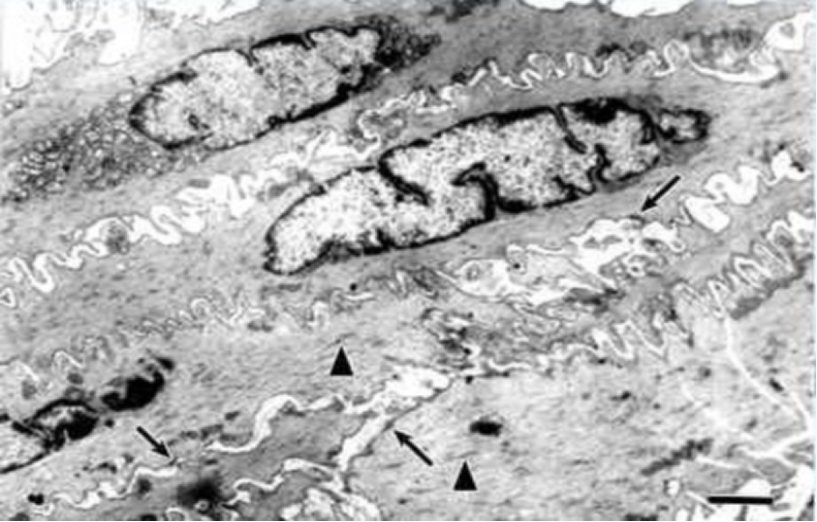

平滑肌纤维透射电镜像:

平滑肌纤维超微结构

1.无肌原纤维,可见粗肌丝和细肌丝及中间丝,若干粗细肌丝聚集形成收缩单位

2.胞膜上有密斑,胞质内有密体,为细肌丝附着处;

3.细胞间有发达的缝隙连接,使功能同步化。